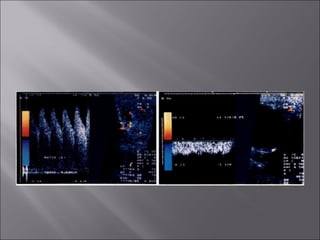

Ultrasound and CT scans provide anatomical images of the orbit, while color Doppler imaging provides visualizations of vascular structures and blood flow within lesions. These imaging techniques are used to evaluate a variety of orbital conditions involving blood vessels, infections, tumors, congenital issues, trauma, and more, and can help identify vascular disorders, thrombosis, treatment responses, and dynamic changes in benign tumors over time.